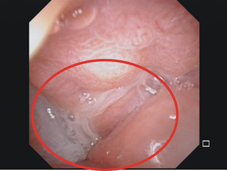

鄭先生是35歲男性,本身無特殊慢性疾病,近年來因為長年聞不到味道,合併有鼻塞情況來本院門診求診,經鼻咽內視鏡診察後發現雙側鼻腔內有鼻息肉(如:圖一),同時合併有膿鼻涕及鼻涕倒流情況(如:圖二)。電腦斷層檢查亦發現兩側鼻竇均有嚴重鼻息肉以及蓄膿情況 (如:圖三),由於過去數月在診所接受藥物治療效果不彰,因此經醫師建議接受電磁導航鼻竇內視鏡手術治療。

圖二、鼻咽內視鏡發現鼻咽部有膿鼻涕及鼻涕倒流情況(紅色圈圈處)